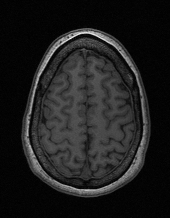

Edge preserving has always been a crucial concern in the design of reconstruction models. To improve the quality of reconstructed images and preserve image edges, some works suggested introducing edge priors in the original restoration problem to preserve image edges [4, 34]. However, they will suffer from complicated algorithm design and time-consuming training processes. Recently, some more efficient methods have been proposed to use edge maps as external guidance for image restoration. For example, Yang et al. [48] used off-the-shelf edge detectors to extract image edges from the degraded images. Fang et al. [12] predicted image edges by constructing an edge reconstruction network. Huang et al. [18] designed a novel dual discriminator GAN framework for solving fast multi-channel MRI, in which one GAN network is built for edge information enhancement. Inspired by these methods, we also consider introducing image edge prior as external guidance to MRI reconstruction since 1) image edges are prominent and distinguishable features in MRI (see Fig. 1), which can serve as a good guide to the model to recover high-frequency details; 2) the ground truth edges can be easily fetched via ordinary edge extraction operators, like Canny, Sobel, and Prewitt, which means that the edge maps can be learned in a data-driven manner. However, how to effectively utilize image edge priors to guide image reconstruction still remains a challenge. In some methods, edge information was simply concatenated with the input image and passed to the next stages. Though this is a simple way to utilize the edge priors, it may not give full play to the guiding role of the edge priors. Therefore, in this work, we want to explore a more efficient and effective mechanism to fully take advantage of image edge priors.

(a)

(b)

(c)

fastMRI is a large-scale MR dataset jointly established by Facebook AI Research and NYU Langone Health. It provides both knee and brain datasets for evaluation. In our work, we use the multi-coil knee dataset, which was acquired on three clinical 3T systems or one clinical 1.5T system using a 15-channel knee coil array. The dataset includes data from two pulse sequences, yielding coronal proton-density weighting with (PDFS) and without (PD) fat suppression. As is shown in Fig. 1, PD images usually contain more structural and prominent edge features than PDFS images, which suggests that it is more challenging to use edge guidance on PDFS datasets. Therefore, we explore the effectiveness of EAMRI on these two modalities. Following [13], for both PD and PDFS knee datasets, we separately filter out 227 volumes (8332 slices) for training and 24 volumes (1665 slices) for testing. The dataset is centrally cropped to .